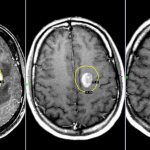

• Computed tomography, magnetic resonance imaging, positron emission tomography help identify focal changes in the brain.

• vascular chorea is easily differentiated: a rapidly developing clinical picture after a cerebrovascular accident, symptoms are one-sided, pathological foci in the brain are visualized on CT or MRI;